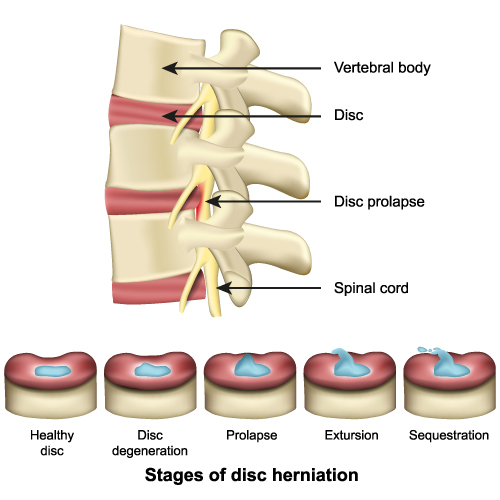

Stages of Disc Herniation

This image provides a two-part visualization related to spinal anatomy and pathology, specifically illustrating a condition known as disc herniation.

The top section of the image shows a side view of the human spinal column, with three vertebrae and the intervertebral discs between them. Each vertebra is labeled as ‘Vertebral body’. The intervertebral discs, which act as cushions between the vertebrae, are labeled as ‘Disc’. Below the disc, the ‘Spinal cord’ runs through the vertebral column. One disc is marked with ‘Disc prolapse’, where a portion of the disc material is protruding outwards, pressing against the spinal cord. This prolapse can lead to pain, numbness, or weakness due to the pressure on the spinal nerves.

The bottom section is labeled ‘Stages of disc herniation’. It shows a progression from a ‘Healthy disc’, which has an intact and hydrated blue nucleus, through stages of ‘Disc degeneration’ where the disc begins to lose hydration and height, to ‘Prolapse’, where the nucleus pushes out against the disc wall. ‘Extrusion’ is the next stage where the nucleus material breaks through the outer layer of the disc but remains within the disc’s confines. Finally, ‘Sequestration’ is depicted as a stage where fragments of the nucleus material have broken free from the disc into the spinal canal.

The sequence illustrates how disc herniation starts from a healthy disc and progresses through stages of deterioration, eventually leading to the extrusion or sequestration of disc material. The health of these discs is critical for spinal function, providing flexibility, shock absorption, and protection for the spinal cord. The progression from a healthy disc to a herniated disc can lead to significant back pain and neurological symptoms due to the impact on nearby spinal nerves.